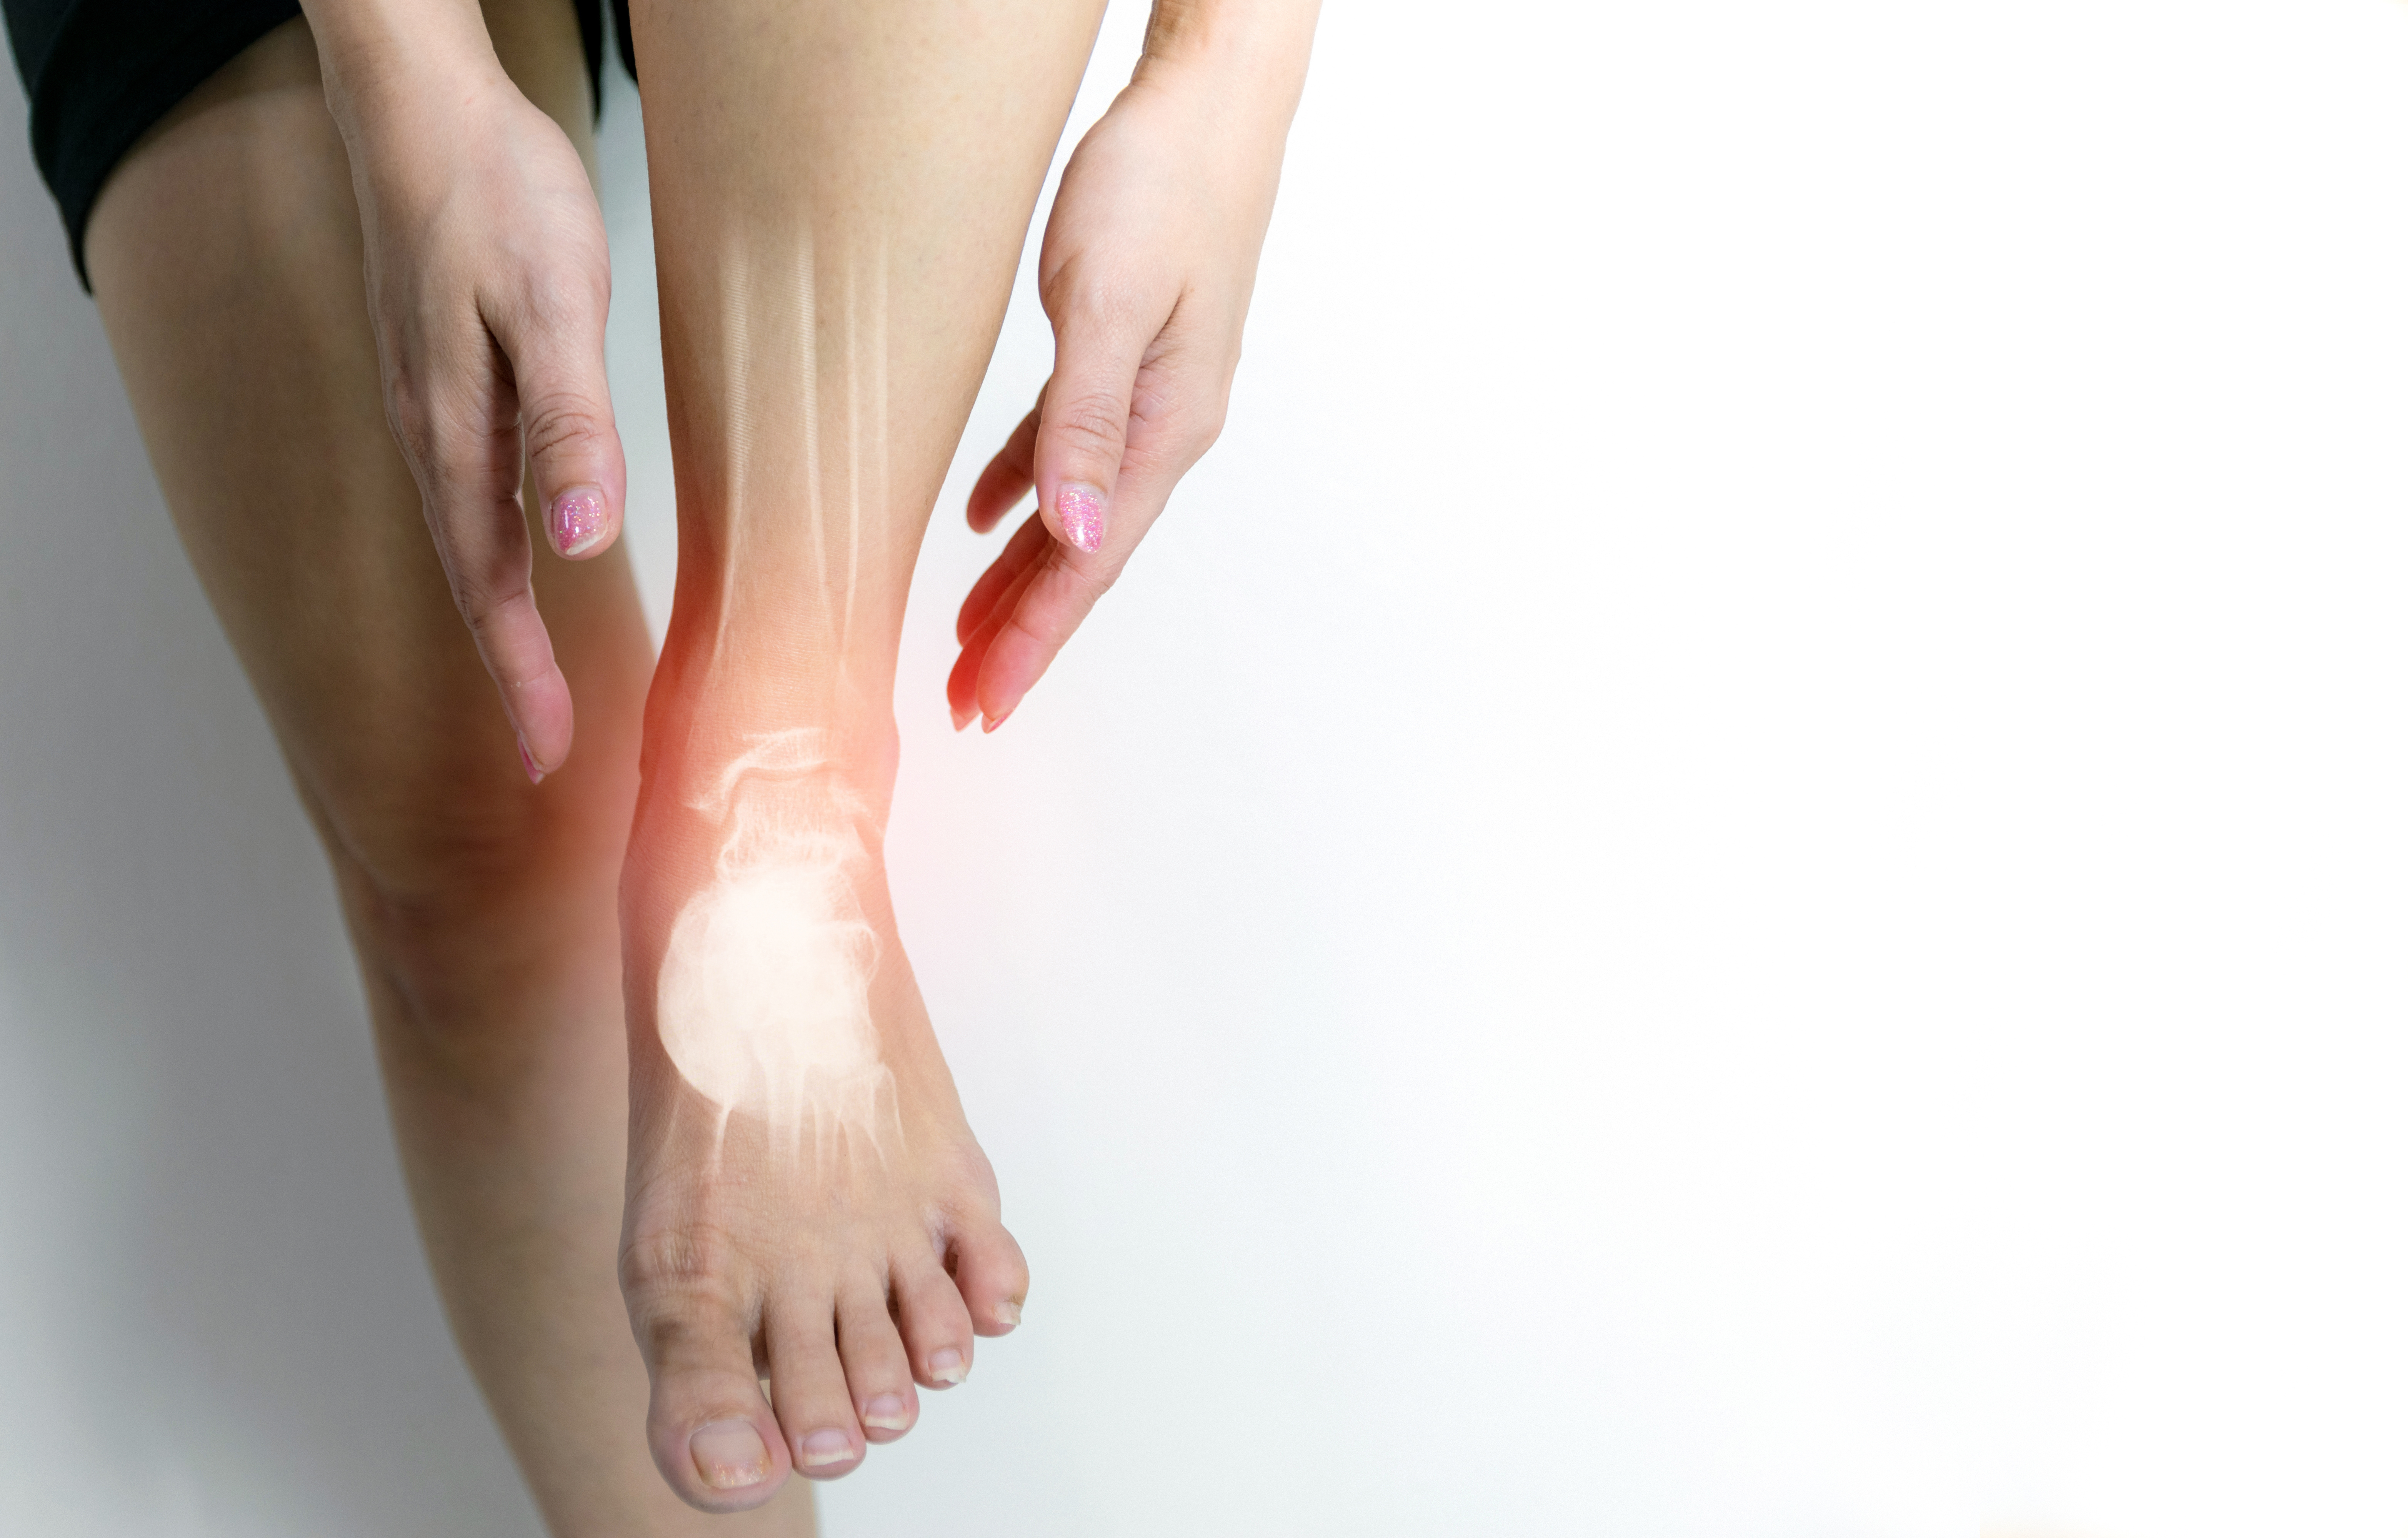

涨知识!外踝骨折可以这样微创入路手术治疗!

FAI手术技巧:严重骨量减少时外踝骨折的复位技术!